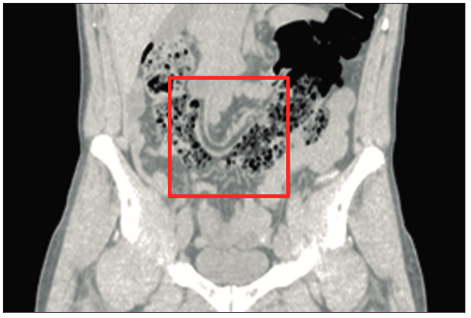

Posteriormente se realiza una tomografía computarizada de abdomen y pelvis sin contraste donde se observan asas intestinales dilatadas (Figura 1), ciego levemente distendido con abundante contenido propio, que cruza la línea media hacia el flanco izquierdo (Figuras 2 y 3), tracción e ingurgitación de los vasos mesentéricos (Figura 4).

Figura 4. Corte coronal. Se observa tracción e ingurgitación de los

vasos mesentéricos